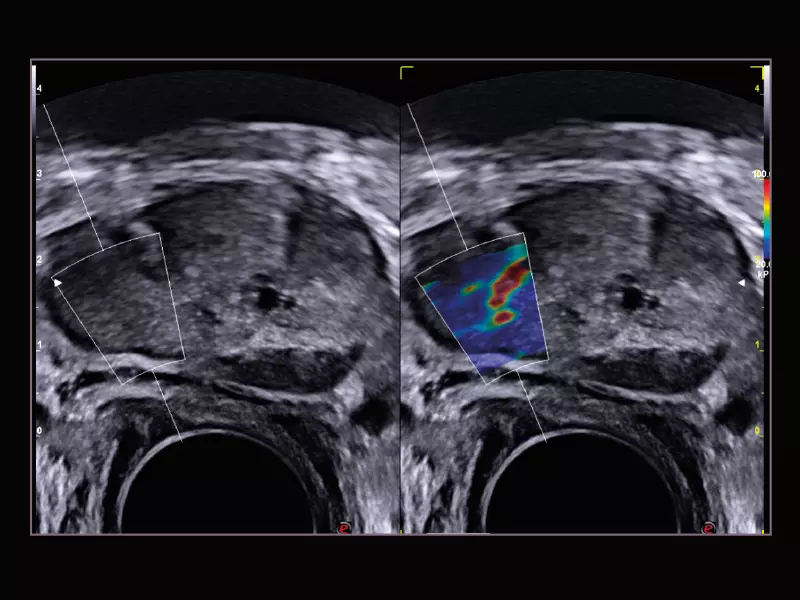

MyLab™X8 Platform - Prostate biopsy with Virtual Navigator fusion imaging 3D

MyLab™X8 Platform - Prostate biopsy with Virtual Navigator fusion imaging 3D